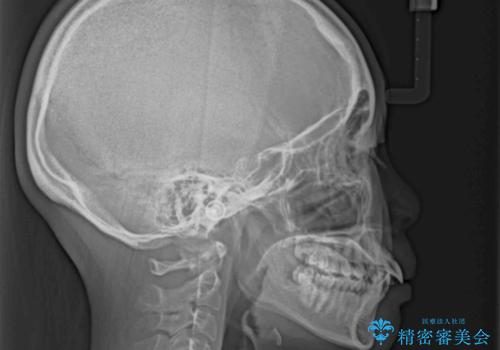

- 口元の突出感を気にして来院された患者様です。

左右ともに上顎奥歯が外を向き、下顎奥歯が内側に倒れているシザーズバイトであったため、補助装置により改善することとしました。

上下の咬み合わせは、下顎に対して上顎が相対的に前方にあったため、奥歯のシザーズバイト改善後に上顎左右第一小臼歯2本を抜歯し、上顎前突を改善していくこととしました。